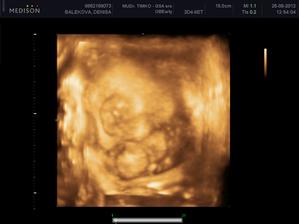

Nas anjelik Alex

Zatial este schovany v brusku ale uz coskoro sa z neho potesime aj nazivo 🙂) Lubime nasho Alexa uz od sameho zaciatku 🙂